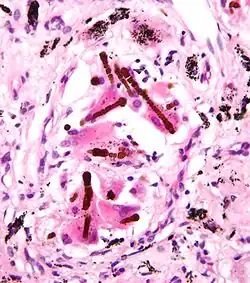

They appear as small brown nodules in the septum of the alveolus. Ferruginous bodies are typically indicative of asbestos inhalation (when the presence of asbestos is verified they are called "asbestos bodies"). In this case they are fibers of asbestos coated with an iron-rich material derived from proteins such as ferritin and hemosiderin.[1] Ferruginous bodies are believed to be formed by macrophages that have phagocytosed and attempted to digest the fibers.

Micrograph of asbestosis with prominent ferruginous bodies. H&E stain.